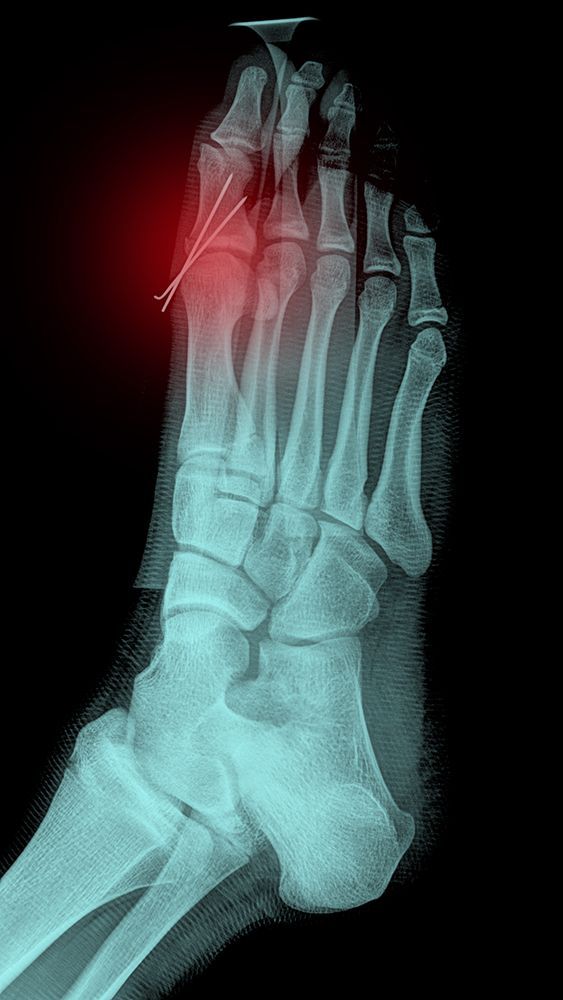

Digital radiology has transformed podiatric care by providing immediate, high-resolution images that allow our podiatrists to identify stress fractures, joint issues, and other abnormalities with precision. Available in both our Bethesda, MD and Springfield, VA offices, digital X-rays give us the ability to view and interpret results right away, ensuring a faster and more accurate diagnosis for painful foot and ankle conditions.

We also use digital X-rays to track changes in foot structure over time, which helps us manage chronic conditions and evaluate treatment effectiveness. In addition, digital imaging may be used to guide surgical procedures and can easily be shared with other physicians involved in your care.